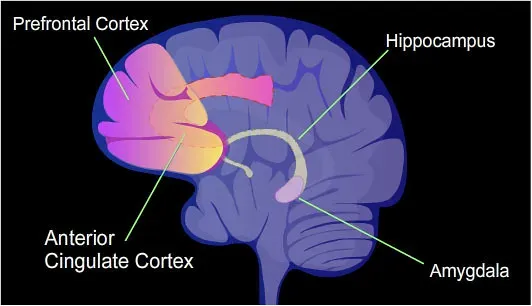

You’ve probably experienced a moment where your heart was pounding before your brain even understood what was happening. That’s not random. That’s the architecture of your emotional circuitry working exactly as designed. Emotion processing often occurs faster than conscious thought. The amygdala can detect threats milliseconds before the prefrontal cortex evaluates them, explaining instinctive reactions. Your ancient alarm system fires before your rational self can even ask, “wait, should I be scared right now?”

Emotions are not governed by a single “emotional center” in the brain. Instead, they arise from a complex network of brain regions working in harmony. Understanding what part of the brain controls emotions requires exploring several key structures, including the amygdala, prefrontal cortex, and limbic system. Think of it less like a single control room and more like a parliament of regions, constantly negotiating. The prefrontal cortex thinks relatively slowly and carefully, with conscious, labor-intensive efforts to figure things out. The amygdala reacts automatically, impulsively, and extremely fast, and its operation is mostly unconscious. The tension between these two systems is essentially the tension between reason and gut feeling – a battle you fight daily.